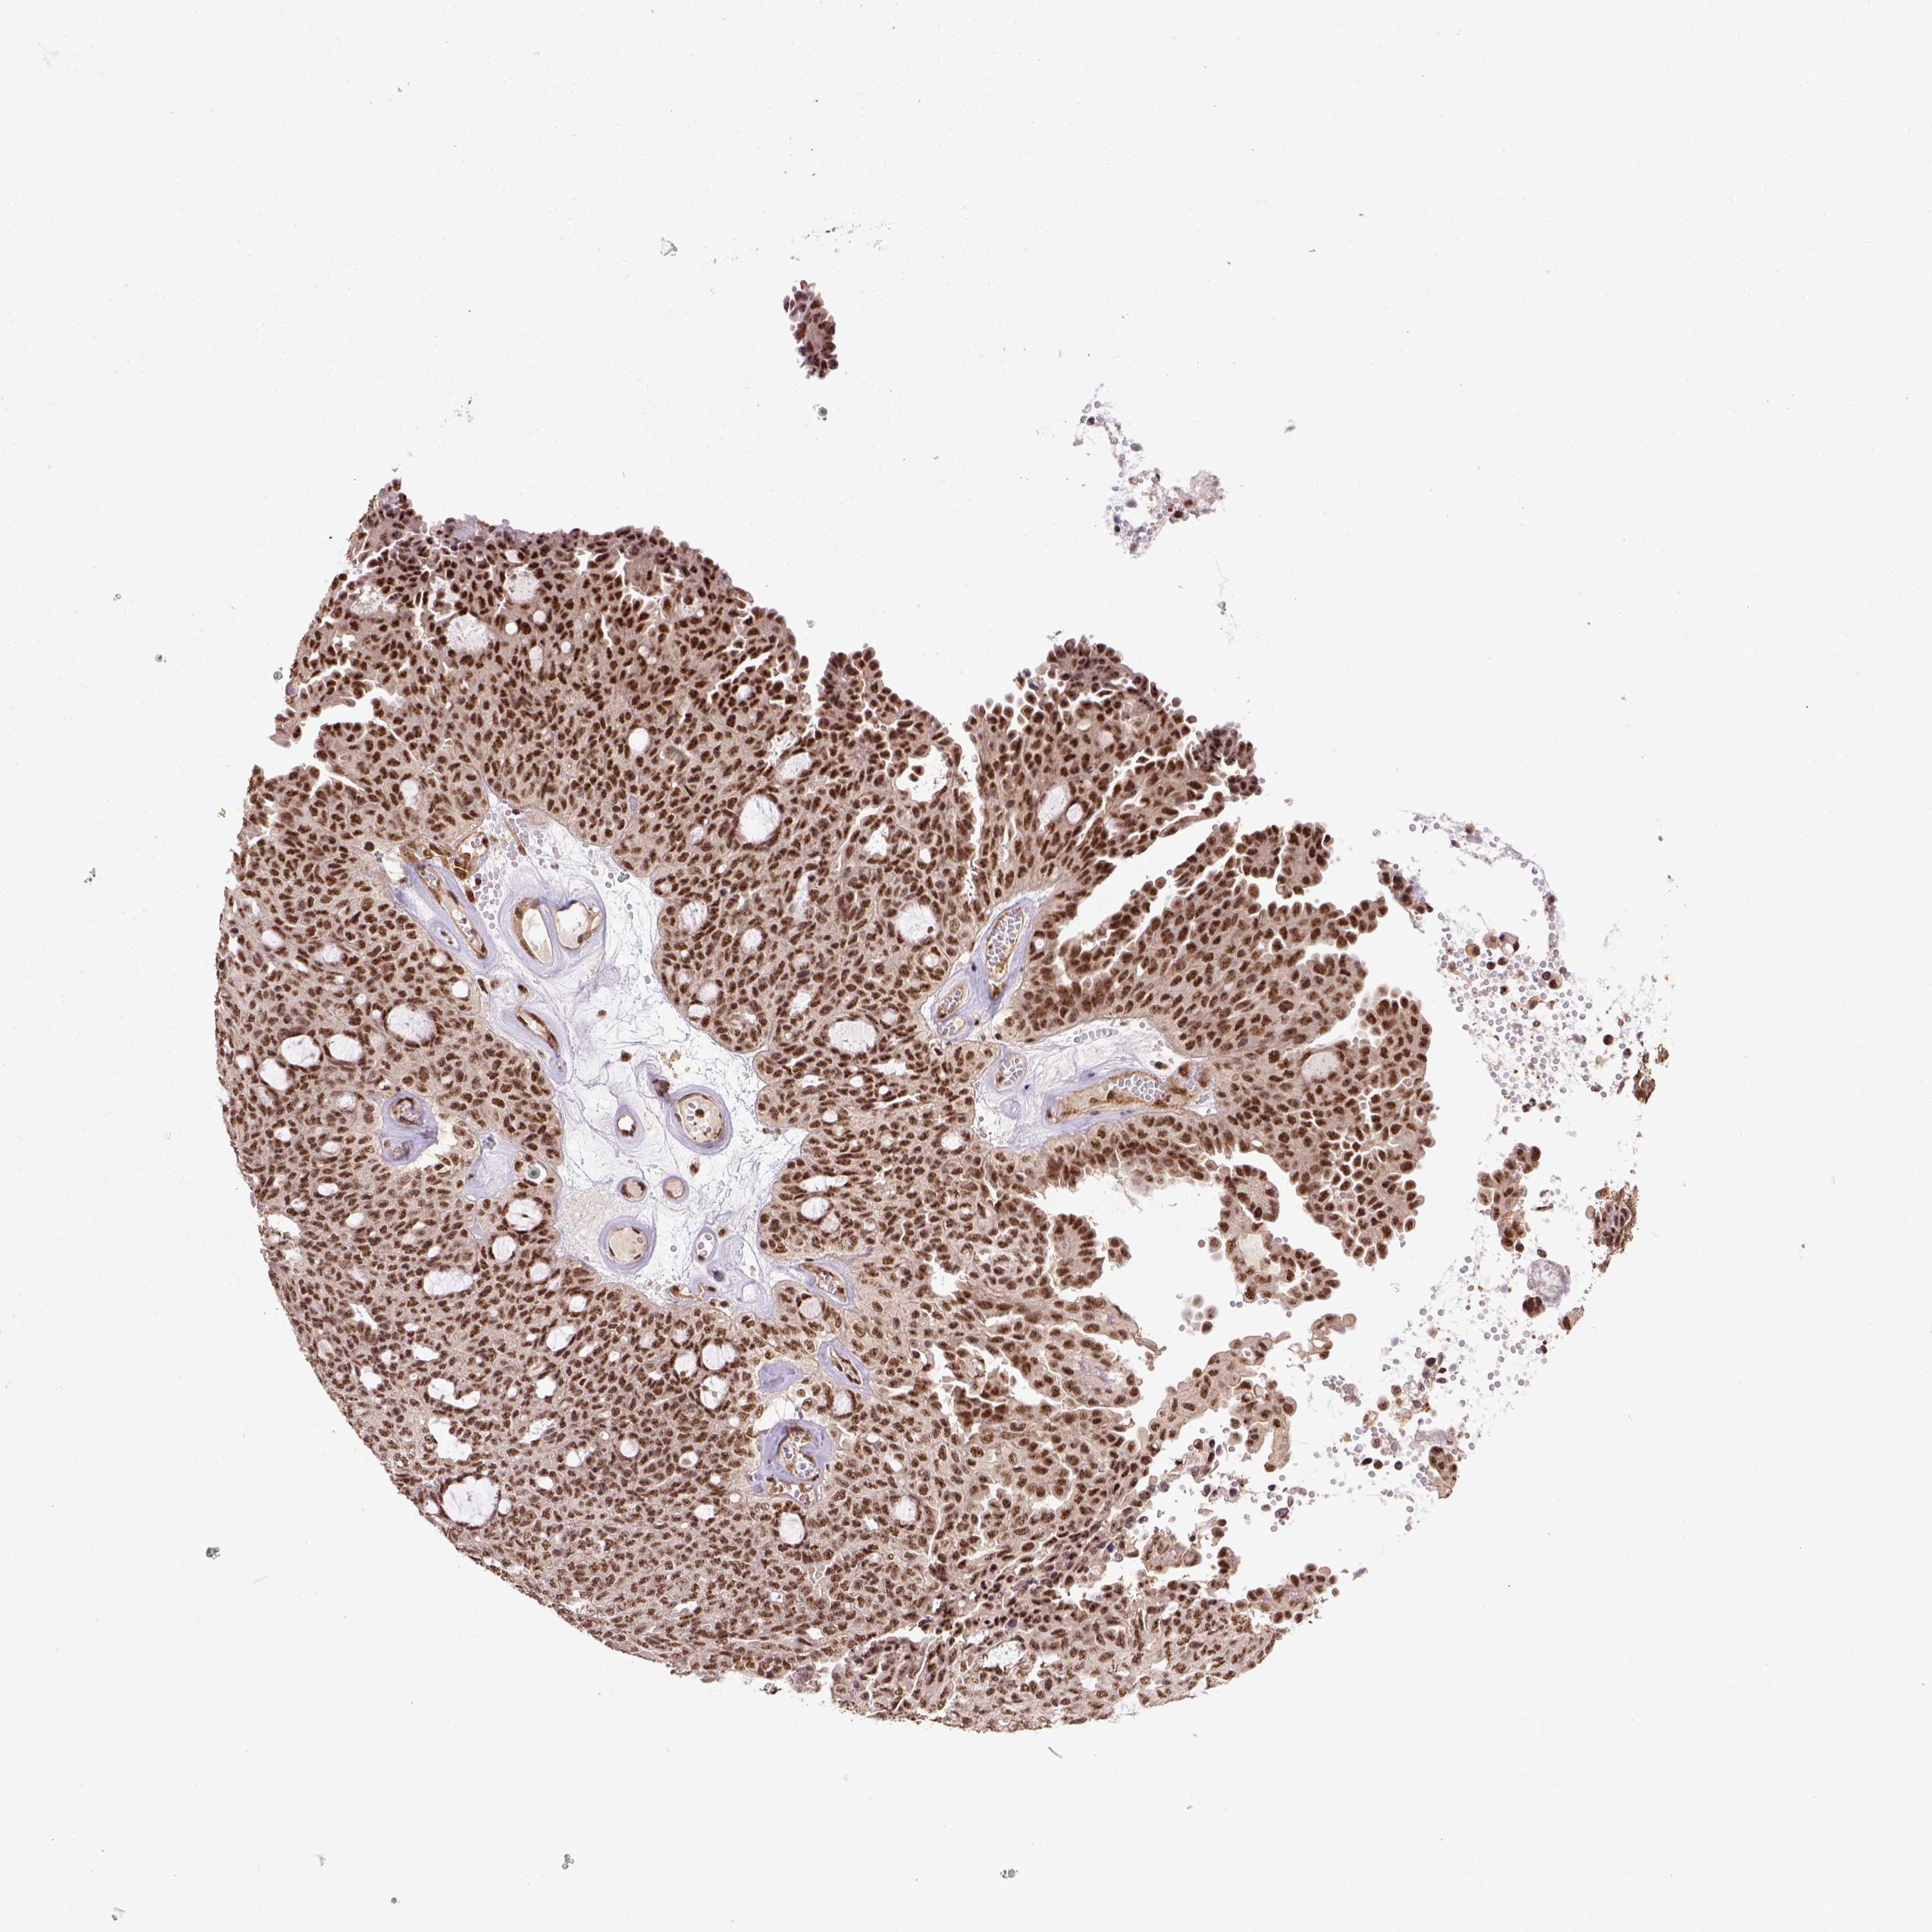

OVARIAN CANCER - Protein expressioni

A mouse-over function shows sample information and annotation data. Click on an image to view it in a full screen mode. Samples can be filtered based on level of antibody staining by selecting one or several of the following categories: high, medium, low and not detected. The assay and annotation is described here.

Note that samples used for immunohistochemistry by the Human Protein Atlas do not correspond to samples in the TCGA dataset.

Antibody stainingi

Antibody staining in the annotated cell types in the current human tissue is reported as not detected, low, medium, or high, based on conventional immunohistochemistry profiling in selected tissues. This score is based on the combination of the staining intensity and fraction of stained cells.

Each image is clickable and will lead to virtual microscopy that enables deeper exploration of all samples and also displays staining intensity scores, fraction scores and subcellular localization as well as patient and tissue information for each sample.

Antibody HPA057469

Staining

High

Medium

Low

Not detected

Intensity

Strong

Moderate

Weak

Negative

Quantity

>75%

75%-25%

<25%

None

Location

Nuclear

Cytoplasmic/membranous

Cytoplasmic/membranous,nuclear

Cystadenocarcinoma, serous, NOS

Cystadenocarcinoma, mucinous, NOS

Carcinoma, endometroid